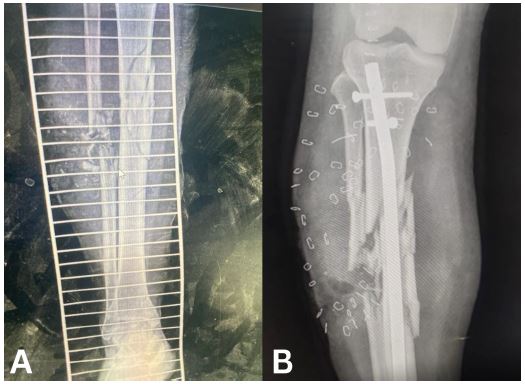

Case 7

Figure 7: (A) Radiograph of external fixator. (B) External fixator and wound at week 3.